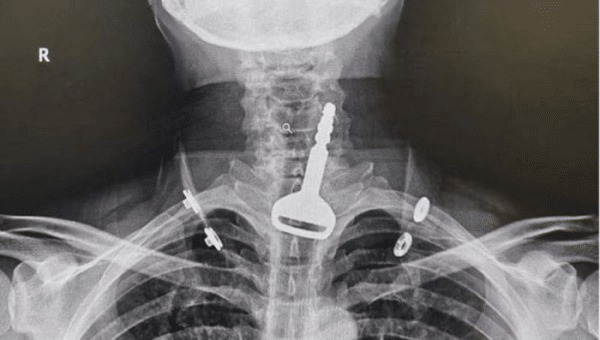

Lelaki ini terpaksa menjalani pembedahan gara-gara tertelan kunci kereta